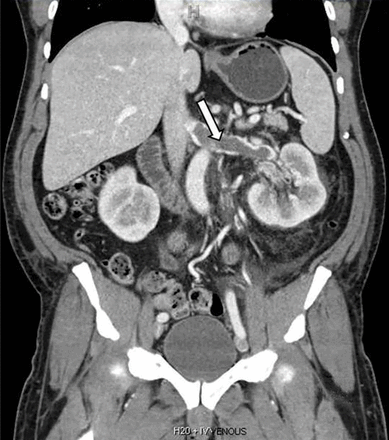

Computed tomography of the chest and abdomen with intravenous contrast demonstrated a nearly occlusive thrombus in the left renal vein (Figure 1) extending to the inferior vena cava with bilateral, nearly occlusive pulmonary emboli (Figure 2).

Coronal reformatted contrast-enhanced computed tomography showed a nearly occlusive low-attenuation filling defect within the left renal vein (arrow).